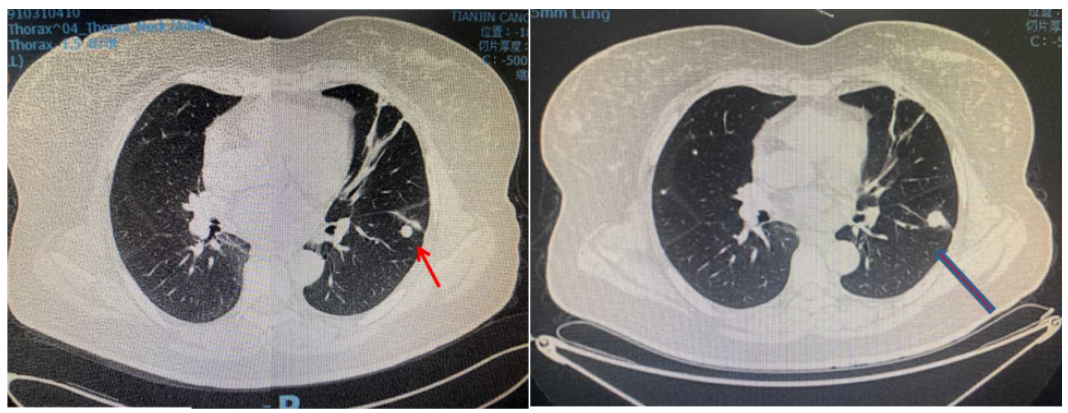

疾病进展:2020年6月,颈、胸部CT显示,双肺多发结节,考虑转移;上腹部强化MRI显示未见明显变化。

疾病进展:2021年1月,颈、胸部CT显示,双肺部分结节较前略增大。基因检测:伴PIK3CA突变。

疾病进展:2021年7月,颈、胸部CT显示,双肺多发结节较前略增大。

2022年7月复查疾病进展,双肺出现新发病灶。